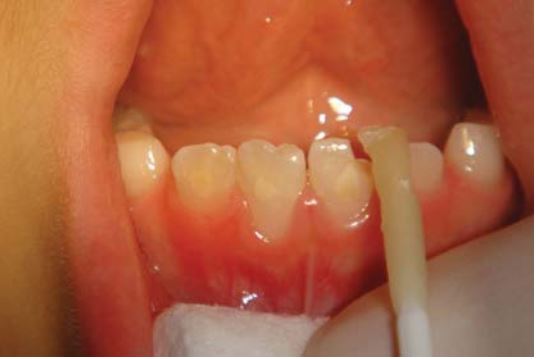

Cả răng cửa và mảnh gãy được khử trùng bằng Chlorhexidine 0.2% trước khi etching và bonding (H18.6 đến 18.11).

Bơm một lớp composite lỏng lên bề mặt răng hoặc bề mặt mảnh gãy để giúp tăng lưu giữ. Sau khi gắn lại mảnh gãy đúng vị trí thì sử dụng dụng cụ để loại bỏ composite thừa (H18.12).